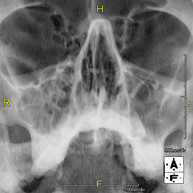

- Paranasal Sinuses X-ray

This technique uses X-ray rendered imaging for examining the paranasal sinuses. Indicated for: difficulty breathing through the nose, chronic cough, headache, mucus.

This technique uses X-ray rendered imaging for examining the paranasal sinuses. Indicated for: headache, chronic cough.